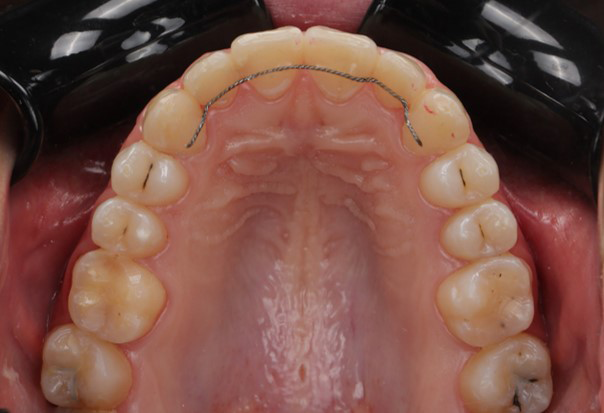

At the end of treatment, the patient’s occlusion was corrected to Class I molar and canine relationships with a physiological overjet and overbite. Irregularities in both arches were eliminated, arch forms were coordinated, and incisor torque was effectively controlled to position the roots centrally within the alveolar bone, enhancing stability. Satisfactory intercuspation was achieved in both the anterior and posterior segments, with maintenance of midline coincidence and periodontal health throughout treatment. The case was finished and transitioned into the retention phase using fixed retainers in the maxillary and mandibular anterior regions.